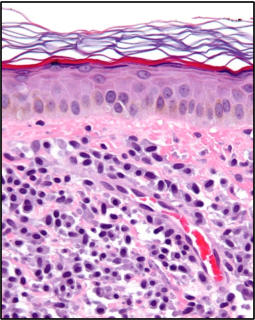

Doktorunuz cildinizin görünümünden deri mastositozu teşhis edebilir ve deri biyopsisinde anormal derecede yüksek sayıda mast hücreleri bularak tanıyı teyit edebilir. Doktorunuz bir kemik iliği kontrolü sırasında, mast hücrelerinin sayısında anormal bir artış bularak sistemik mastositozu teşhis edebilir. Mastositozlu şüpheli bir vakada kandaki mast hücrelerinden bir protein (triptaz) ölçülebilir veya bu hastalıkla ilişkili belirli genetik mutasyonları aranabilir.